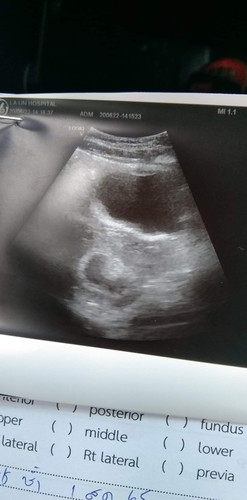

ไม่เจอตัวอ่อน😔🥲

6วีคแล้ว อัตซาวมาไม่เจอตัวอ่อนเลยค่ะ แม่บ้านไหนเป็นแบบนี้บ้างค่ะ 😔😔

อย่าพึ่งกังวลมากค่ะ อายุครรภ์อาจยังน้อย ของเราตรวจเจอครั้งแรกตอน9w ก็เจอแต่ถุงตั้งครรภ์ยังไม่เจอตัวอ่อน เจออีกที11wค่ะ สู้ๆนะคะ✌

บ้านนี้เจอตัวน้อง 8w ค่ะ

รอ สัก 12 วีคนะคะ